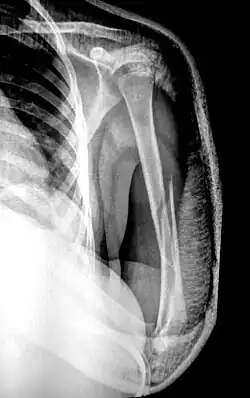

Рентгенограмма при переломе хирургической шейки плеча. Возможен перелом головки, отрыв малого или большого бугра, перелом анатомической и хирургической шейки плеча. Наиболее распространены переломы хирургической шейки, причём подавляющую часть пострадавших составляют люди пожилого возраста. Причиной перелома обычно становится падение на локоть, плечо или отведённую руку.

Пациент предъявляет жалобы на боли в области плечевого сустава. Вколоченные переломы сопровождаются нерезким отёком, болезненностью при попытке активных движений. Пассивные движения ограничены незначительно. При переломе со смещением клиническая картина более яркая. Пострадавшего беспокоят выраженные боли. Выявляется умеренный отёк, деформация области сустава и укорочение конечности. Определяется крепитация (хруст костных фрагментов). Диагноз уточняют по результатам рентгенографии.

При вколоченных переломах руку фиксируют специальной повязкой. При переломах хирургической шейки со смещением выполняют репозицию под местной анестезией. В последующем возможна фиксация повязкой по Турнеру или на отводящей шине, лейкопластырное или скелетное вытяжение. ЛФК назначают, начиная с 7-10 недели лечения. Срок иммобилизации составляет 6 недель.

Операция показана при нестабильных и оскольчатых переломах. Противопоказанием к операции является старческий возраст и тяжёлые хронические болезни.